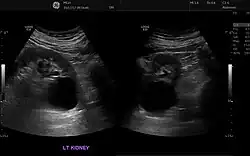

Ecografía renal

Se utiliza para obtener imágenes de los riñones, los uréteres y la vejiga. Se realiza este examen cuando los médicos sospechan de alguna problema renal y este les permite identificar:

• el tamaño de los riñones

• lesiones

• anomalías presentes desde el nacimiento

• obstrucciones o piedras en los riñones

• complicaciones por infección en el tracto urinario

• quistes o tumores[19]